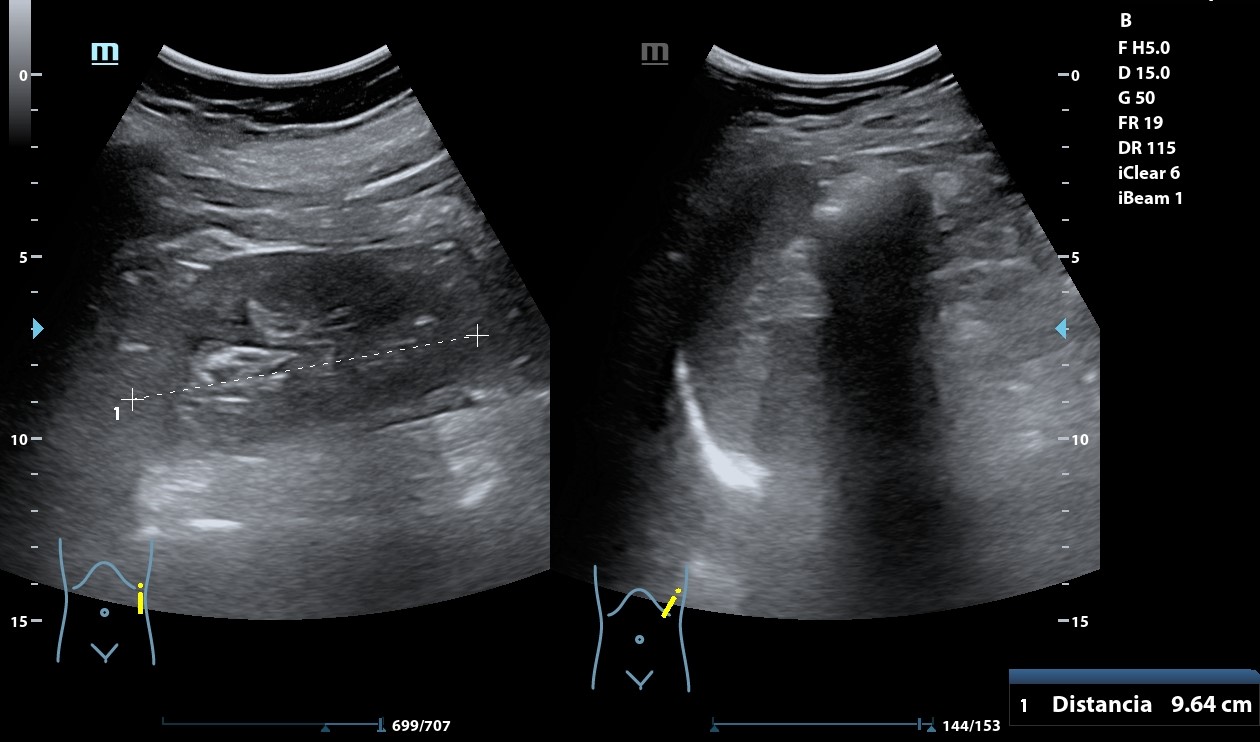

Hígado con abundantes LoEs hiperecogénicas con halo hipoecogénico. Retroperitoneo con abundantes imágenes redondeadas, hipoecogénicas peripancreáticas y retroperitoneales que llegan a medir 28 mm. A nivel de fosa ilíaca izquierda se observa imagen en pseudoriñón que con Doppler presenta captación y llega a medir hasta 72,2 mm.